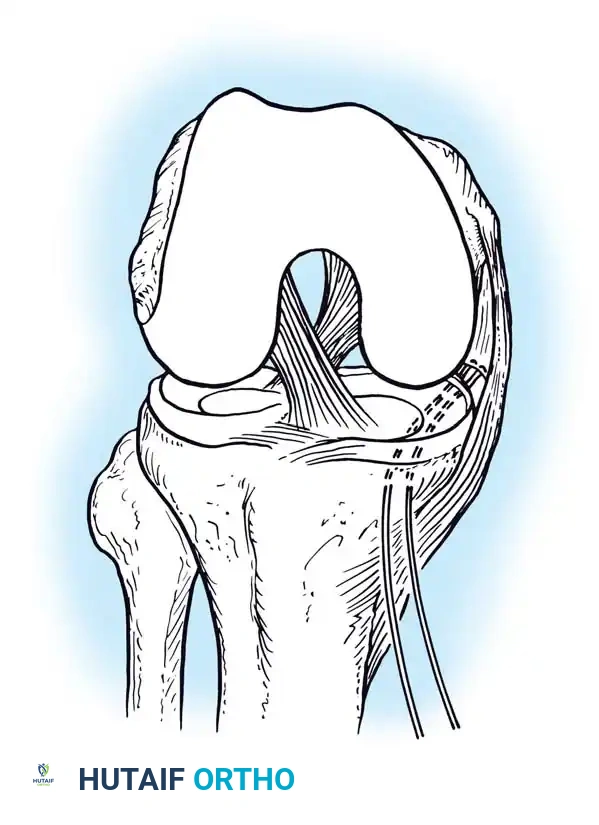

In cases where the native tissue is non-viable or the injury is subacute, an anatomical posterolateral corner reconstruction using an autograft or allograft (e.g., Achilles or semitendinosus) is mandated. The graft is routed to recreate the LCL and popliteofibular ligament.

Image

Robust fixation is achieved using interference screws or screw-and-washer constructs in the fibular head and lateral femoral condyle. The biomechanical integrity of the construct is verified by taking the knee through a full range of motion, ensuring no impingement or laxity.